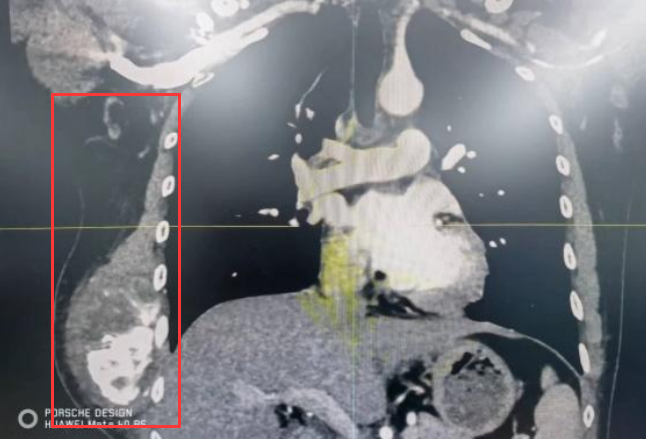

36岁的李先生(化名)半年前发现自己右侧胸部有个隆起的硬包,因没有明显不适就没有在意,但随着时间的推移,硬包越长越大,遂到中大五院胸外科就诊。完善相关检查发现为右侧胸壁软骨肉瘤,大小约16cm*12cm。

中大五院外科主任兼胸外科主任曹庆东教授介绍,胸壁软骨肉瘤属于恶性肿瘤,如不尽快采取措施,肿瘤将持续增大压迫周边组织,有癌细胞扩散转移的风险。幸运的是,患者肿瘤没有发生远处转移,采用根治性手术切除是首选治疗方案。

但患者的右侧胸壁肿瘤较大,手术既要完整切除胸壁软骨肉瘤,又要重建大块缺损的胸壁,手术难度大、风险高。随后,胸外科联合创面修复与烧伤外科、麻醉科、胸部肿瘤科、病理科、放射科等科室专家进行了多学科会诊,最终决定由胸外科联合创面修复与烧伤外科行“右侧胸壁软骨肉瘤切除+胸壁重建术”。